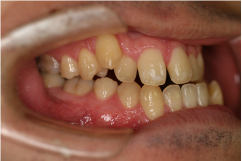

叢生 / そうせい

「八重歯」や「乱ぐい歯」のこと。八重歯は犬歯が飛び出している状態で、乱ぐい歯は歯並びがデコボコな状態です。

症例名

叢生(そうせい)

治療前

治療後

| 主訴 | 著しい乱ぐい歯、口元の突出 |

|---|---|

| 診断名 | 著しい叢生のClass l不正咬合 |

| 初診時年齢 | 21歳1か月 |

| 主な治療装置 | マルチブラケット装置、歯列弓拡大装置 |

| 抜歯部位 | 上下顎左右第一小臼歯の抜歯 |

| 治療期間 | 2年1か月 |

| 治療費 | 矯正治療基本料:60万円 / 調整料 3,000~5,000円×35回 |

| リスク・副作用 | 矯正中は、口腔を清潔に保たないと、虫歯、歯肉炎、歯周病になるリスクがあります。マルチブラケット装置の使用には、口腔内の刷掃や治療協力が必要です。成人では、強い歯ブラシ圧によって歯肉退縮が起こることがあるので注意して下さい。治療後の保定を怠ると、このような症例では、後戻りが容易に起こるので長期管理が必要です。 |